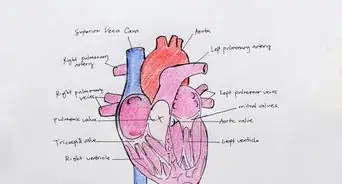

- In addition to these structures, draw an overlay of the pulmonary artery (red) and pulmonary vein (blue) leading into the arteriole and venule capillary system.